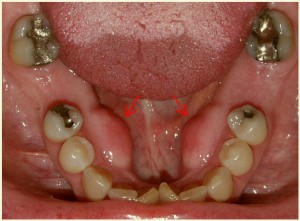

Экзостозы нижней челюсти симметричные — костные образования различной величины и формы, расположенные симметрично на язычной поверхности нижней челюсти против премоляров. Причины их проявления неизвестны. Экзостозы разрастаясь, представляют определенную трудность при протезировании съемными протезами, поэтому иногда их приходится удалять. Если нижняя челюсть беззубая, то удалению подлежит экзостоз только с одной стороны.